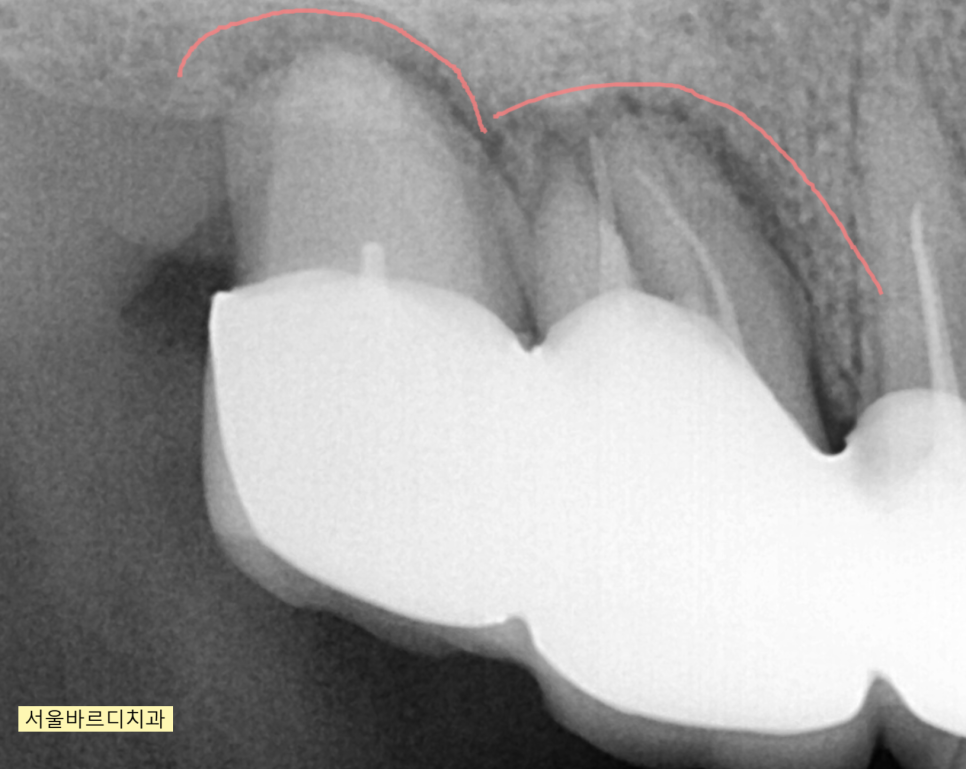

230630 녹은 경계를 확인해주세요!

x-ray 상에서도 뼈가 녹은 부분과

녹지 않은 부분이 경계져 보이는 것이 관찰되실겁니다.

녹은 부분은 까맣게 되어있고

괜찮은 부분은 하얗게 말이죠.